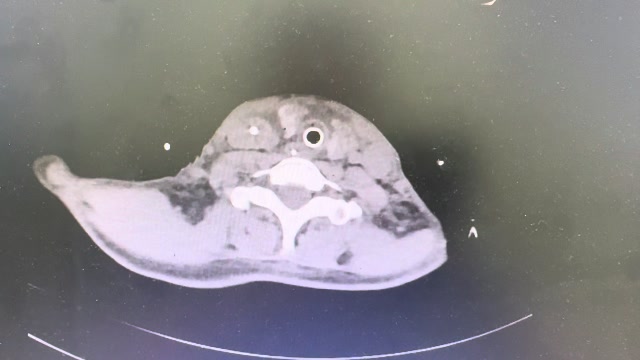

辅助检查